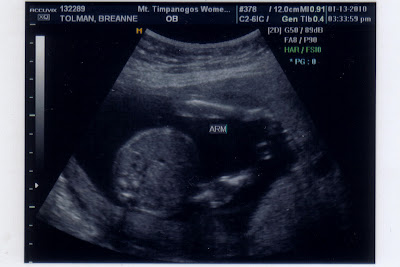

That's exactly what I was yesterday.  I had a certain gender in mind and thought that I was 100% right for a very long time and learned that I was completely WRONG!!!!  It's been almost a full day and I think it will take me awhile longer to really believe the Ultrasound.

That's right!  We're having a GIRL!!!!!

I'm just completely floored, but excited.  She really is a very huge blessing because I don't have to buy ANY clothes for her (Mara's bday is in April, and she is due in June).  Hopefully there's enough of a span between the girls that Mara won't feel threatened when she's old enough to want to play with Mara's princess toys!